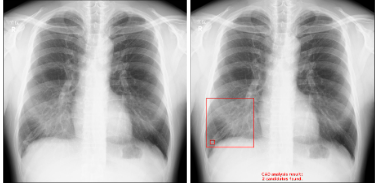

【画像例】

・浸潤影の内側に結節影がある症例